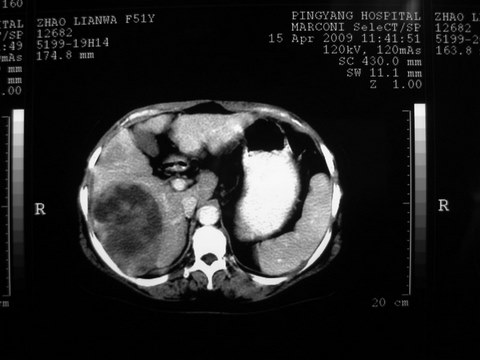

患者 女 51岁 两天前感觉上腹疼,无明显诱因,b超示肝右叶囊实性占位,边缘清楚,其内回声不均匀,ct增强如图,大家看看是什么 ,病人一年前及两月前b超检查只是提示胆囊炎

外院术后,证实肝癌合并出血

特点:1,病灶发展迅速,(2月前正常)[br] 2,囊实性,且并边界清晰光滑,呈右后叶赘生性。囊性区无强化,实性部分较多轻度强化,边界欠清。考虑囊腺癌或囊腺瘤。

出病理 中分化肝细胞癌合并出血